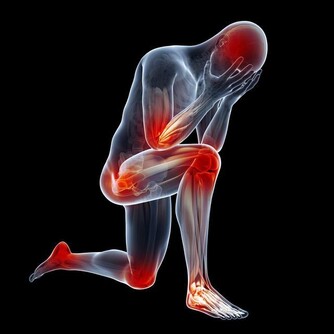

▼請大家先回想自己坐在馬桶時的情形,是不是膝蓋和身體保持大約90度的姿勢呢?以坐姿排便時,幫助控便的恥骨直腸肌因為姿勢的問題無法放鬆,從而導致了如廁時的困難;相反地,若是以身體和膝蓋呈現110度的蹲姿排便時,恥骨直腸肌才能完全疏鬆,在一定程度的腹壓幫助下,糞便就能更輕易地從體內排出。

▼有便秘問題的朋友們大部分也會因為不良排便習慣而面對長痔瘡的困擾,有些人只是在排便時輕微出血;但嚴重者分分鐘會因為這小小一顆「痘痘」而痛苦不堪,連行動都成問題。如果你真的不想要因為痔瘡問題去動手術的話,那就趕緊用蹲姿上廁所!